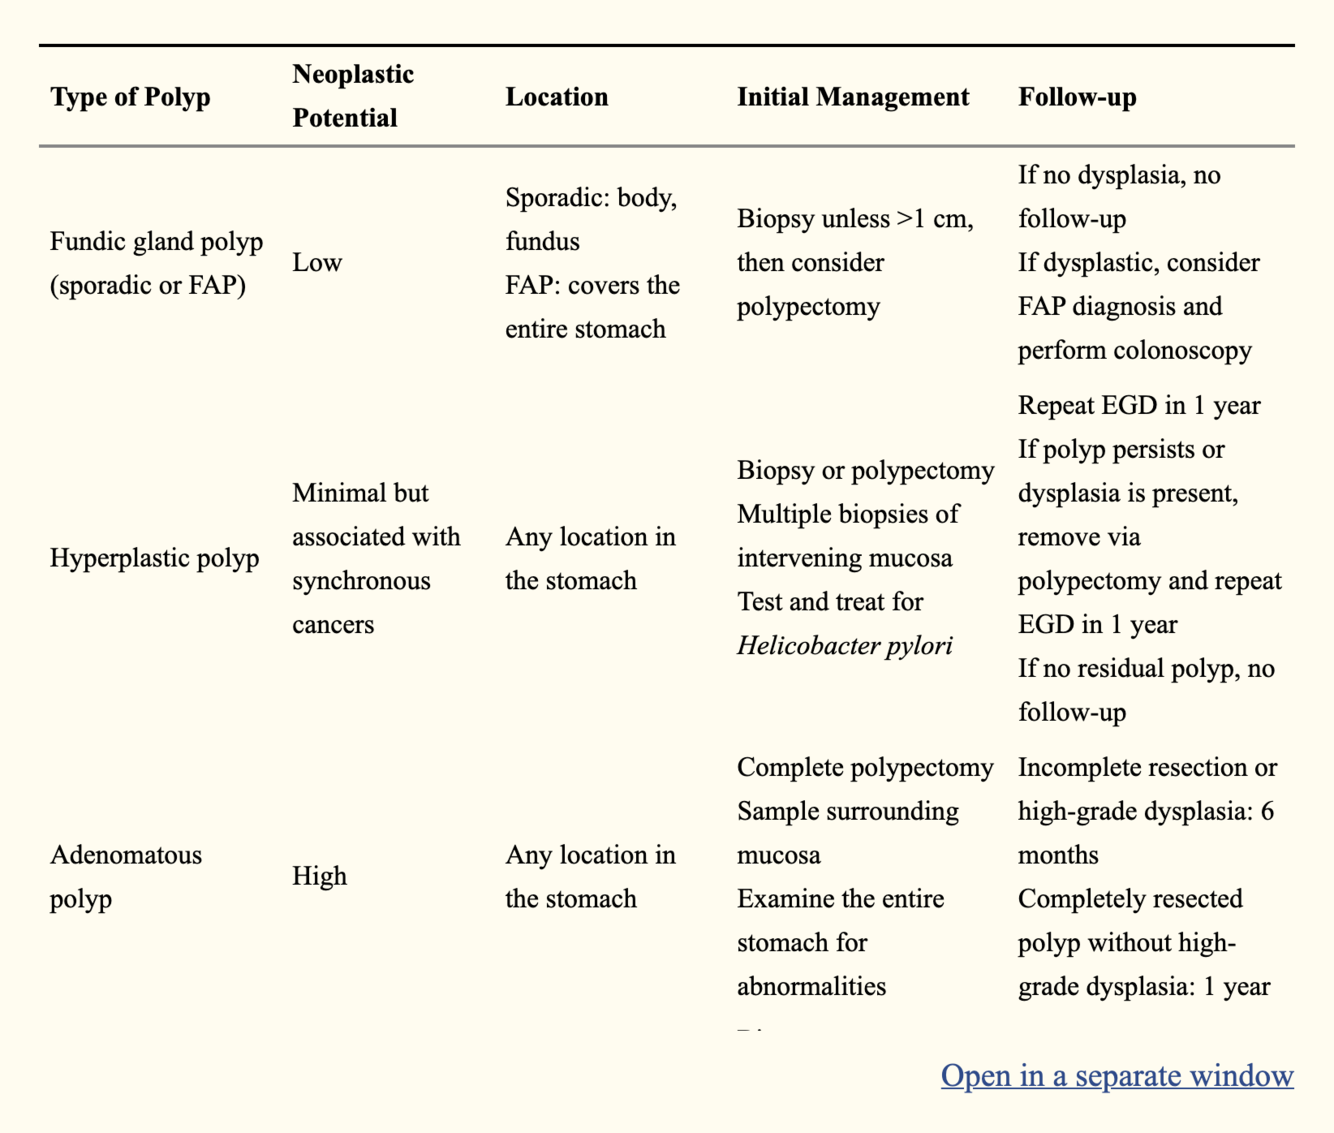

Gastric Polyps

- Incidence

- Types

- Incidence

- GPs are far less common than colonic polyps

- 2% of all patients with polyps

- Types

- Hyperplastic Polyps

- 80% of all gastric polyps

- <1cm

- Sessile

- Not premalignant

- A/w

- chronic atrophic gastritis

- Familial adenomatous polyposis (hyperplastic polyps in the stomach, adenomatous polyps in the colon

- typically similar size, multiple, and clustered in the fundus and body.

- Synchronous gastric carcinoma in 5-25% of patients.

- Adenomatous Polyps

- Infrequent

- malignant degeneration 50%

- solitary

- Villous polyps

- uncommon

- cauliflower like

- sessile

- Stong malignant potential

- hamartomatous polyps

- peutz-jeghers

- cronkhite-canada suyndrome

- juvenile polyposis

- Hyperplastic Polyps

- https://www.ncbi.nlm.nih.gov/pmc/articles/PMC3992058/